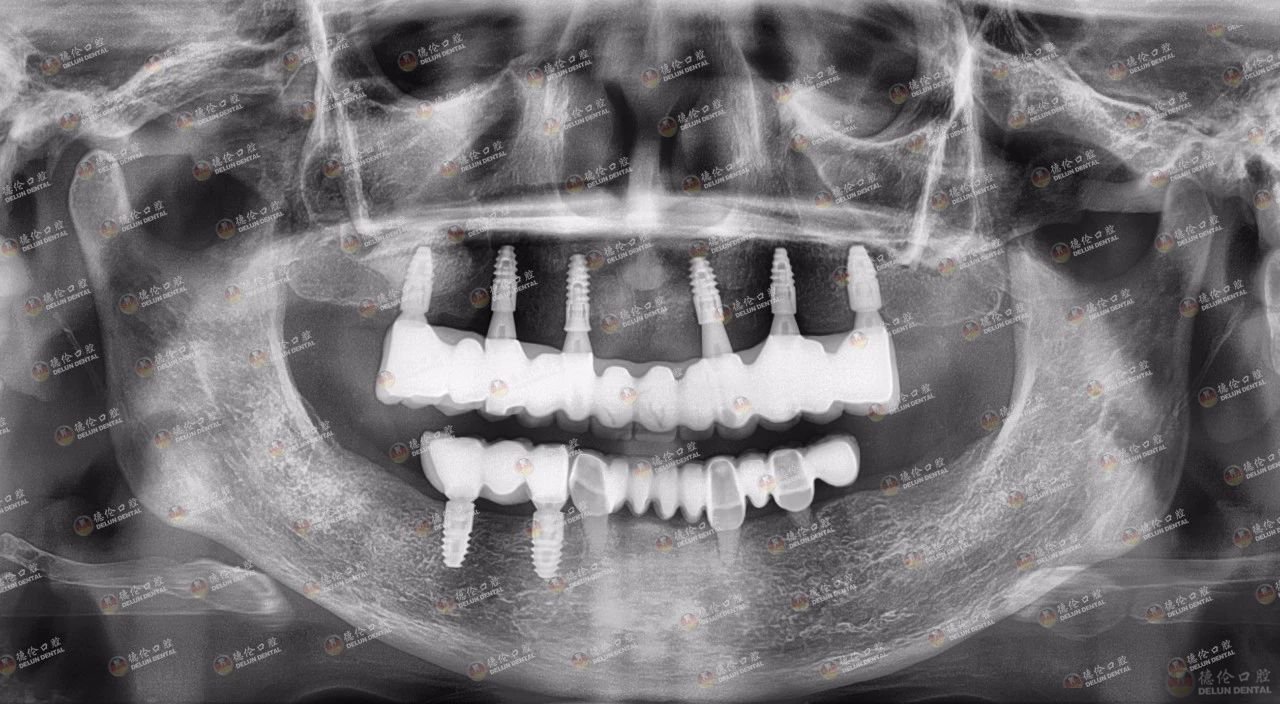

在医护团队的安抚和支持下,程武主任用高配版数字化种植技术为吴女士的上下颌共计植入了8颗种植体,一年多的时间过去,种植牙功能良好、使用方便,只要护理得当相信会一直伴着吴女士,实现她的百岁好牙梦想。

吴女士种植带冠后的牙片显示,种植体就位准确,受力均衡